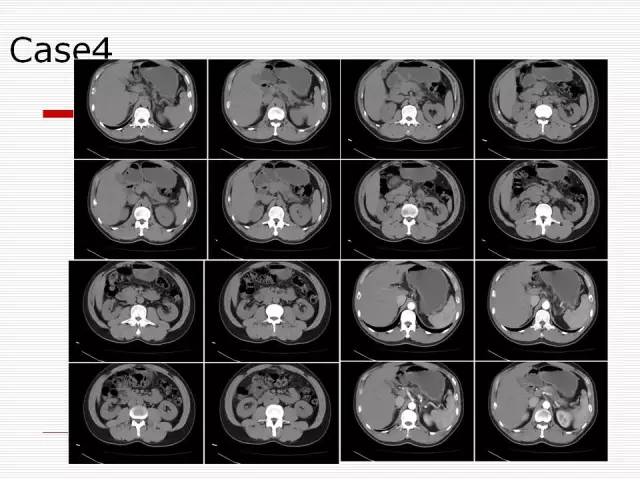

Case4:男,55岁,发现胰腺占位来就诊

Case 4

Case4: 胰腺癌囊性变

胰腺癌囊性变:多由肿瘤组织阻塞导管引起潴留性囊肿或由肿瘤发生坏死液化而形成囊腔。

潴留性囊肿的近端常有实性肿块,肿瘤坏死囊变,肿瘤实性组织构成囊壁,故囊壁不完整,厚而不规则,或无明确囊壁显示。